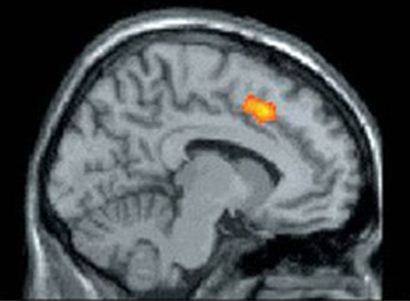

Anterior Cingulate Cortex, disingkat ACC. Posisinya di bagian otak depan dan bertanggung jawab memberikan rasa sakit terhadap tubuh setiap kali kamu merasa terkucilkan dalam lingkungan sosial. ACC juga merupakan bagian otak yang aktif kalau fisik kamu merasakan sakit, seperti dicubit atau ditampar. Sesimpel kalah main game aja bisa membuat si ACC ini bereaksi (Lebih-lebih lagi ditinggal kekasih hati). Secara fisiologis hal ini menunjukan betapa kita sebagai manusia sangat membutuhkan hubungan sosial. Nah, mengingat ACC ini juga merupakan bagian otak yang aktif kalo fisik merasakan rasa sakit, maka rasa sakit yang ditimbulkan saat patah hati ini juga benar terasa.

Bagian seuprit yang berwarna oranye diatas itu yang dinamakan ACC. Silahkan salahin doski yang bikin hati kamu serasa diperes-peres tiap kali ngalamin sakit hati.